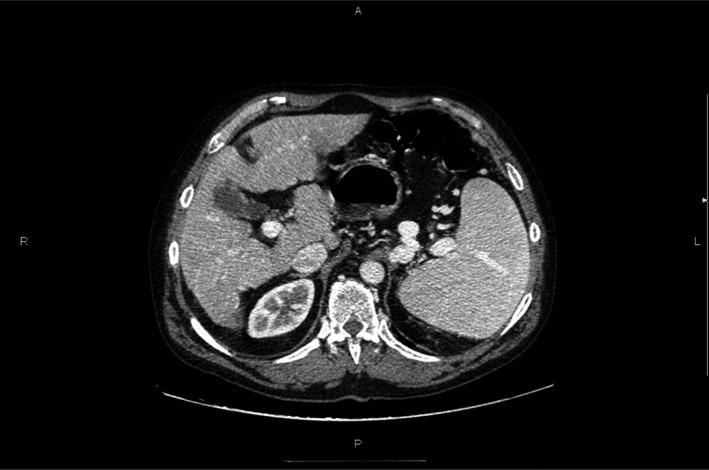

Our case report discusses the usefulness of administering romiplostim as a second-line treatment before splenectomy in a cirrhotic patient with immune thrombocytopenia who developed corticosteroid-induced Cushing's syndrome. Corticosteroids were tapered and consequently withdrawn. The patient made a full recovery postsplenectomy.

https://cdn.ncbi.nlm.nih.gov/pmc/blobs/5369/5290496/da0ffe3448bb/CCR3-5-159-g001.jpg